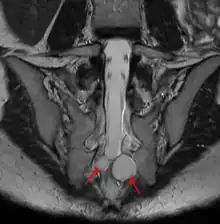

MRI sagittal image of sacral and dorso-lumbar perineural cysts.

MRI, or Magnetic Resonance Imaging, is considered the imaging study of choice in identifying Tarlov cysts. MRI provides better resolution of tissue density, absence of bone interference, multiplanar capabilities, and is noninvasive. Plain films may show bony erosion of the spinal canal or of the sacral foramina. On MRI pictures, the signal is the same as the CSF one.

If MRI made with a contrast medium:

• The signal in the cyst is the same as in the dural bag.

• The signal for cysts due to traumas is a little stronger at the periphery or nerve root location.

• The signal is more important for other causes: synovial cysts, dermoïdes or épidermoïdes cysts, teratomes.[7][25][26]